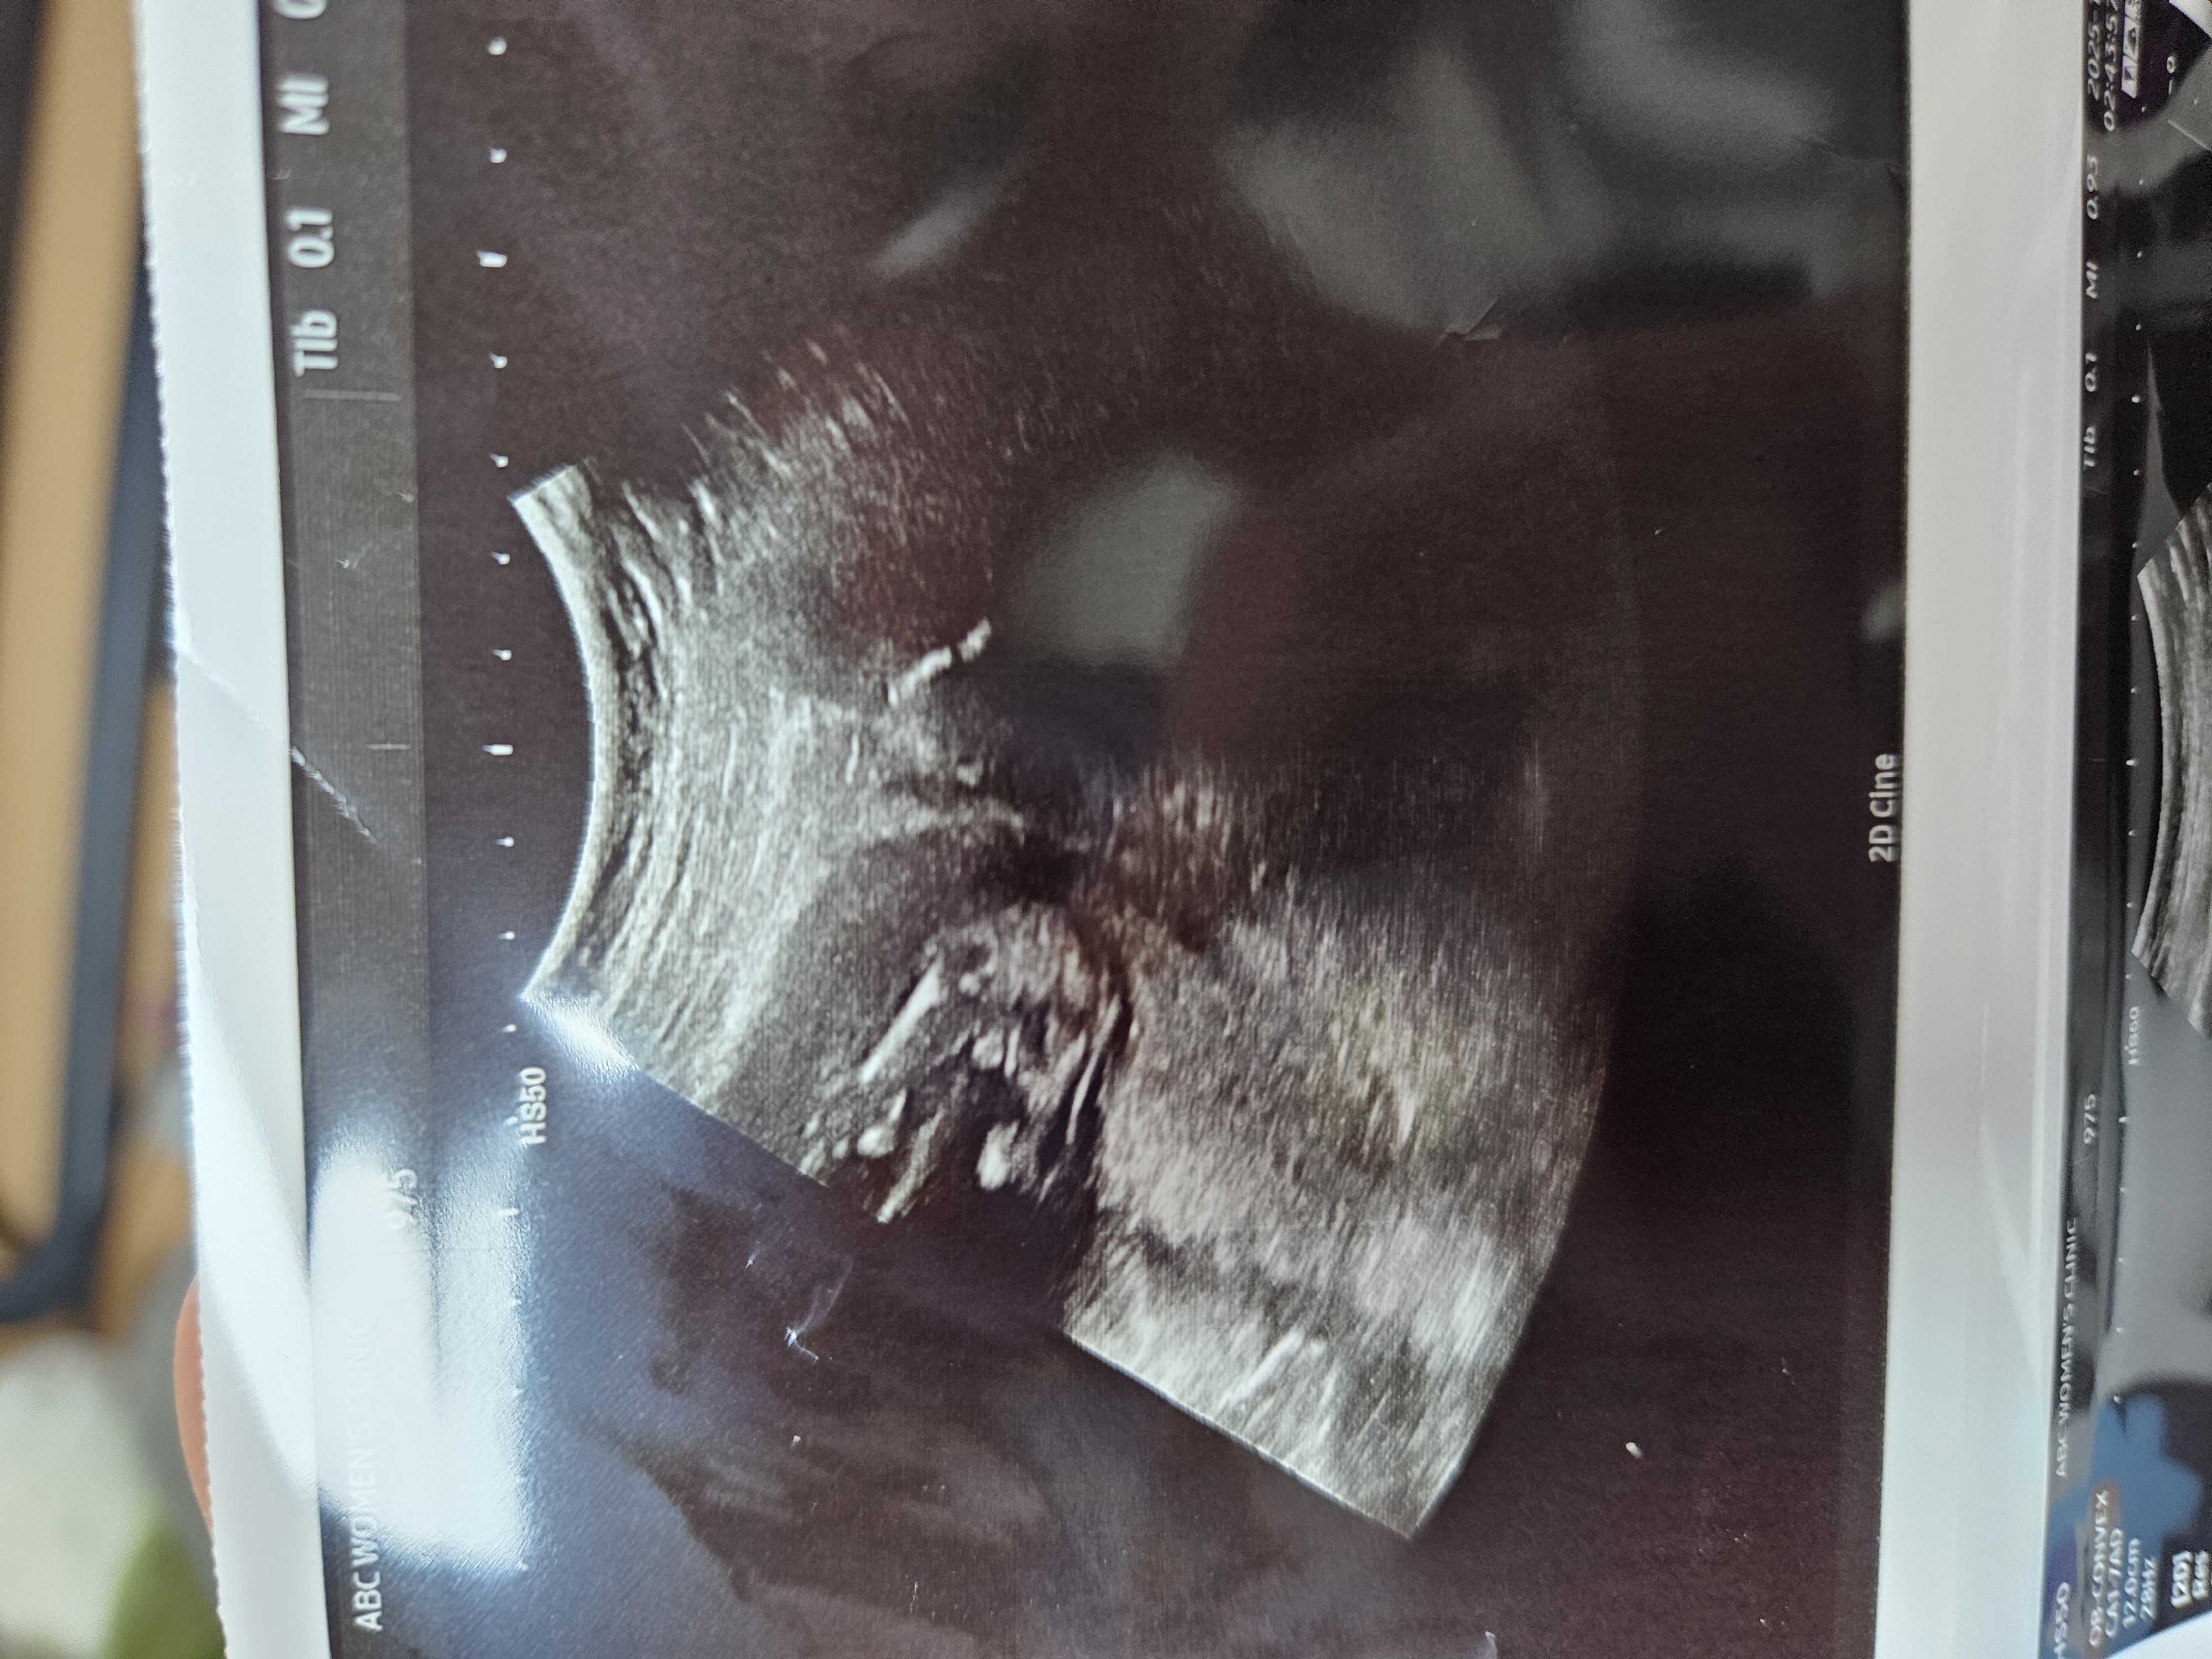

14주 초음파 성별 봐주실분♡

다리 사이에 동그랗게 보이긴 하는데 애매하죠...? 둘째라 성별 너무 궁금해요!

저정도면 안애매하지않을까요..아들 ㅎㅎ

아들이요

아들같아용!◡̈